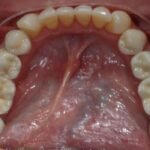

Punto Bajío Casos Clínicos Prótesis Fija sobre Implante unitario Inicio Provisional Final Prótesis Parcial Fija sobre 2 Implantes 2 Implantes Final Prótesis Bucal Removible Inicial Inicial Superior Inicial Inferior Rayos X Inicial Rayos X Inicial Frontal Final Final Superior Final Inferior Prótesis Parcial Fija/ Coronas de Circonio Sonrisa Inicial Foto Inicial Foto Inicial Inferior Foto Final Inferior Foto Final Sonrisa Final Prótesis Total Protesis Inmediatas 1 Protesis Inmediatas 2 Prótesis Removible/ Coronas Metal-Ceramica Carillas Incrustaciones Endodoncia